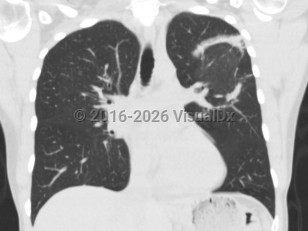

Drug-induced pneumonitis

Cryptogenic organizing pneumoniaCryptogenic organizing pneumonia